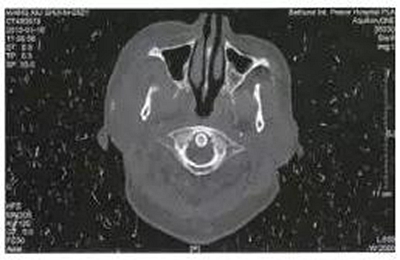

病例2,女,28歲。于1月前拔除右側(cè)上頜第三磨牙,3天后出現(xiàn)右側(cè)顳部劇烈疼痛,張口度15 mm,經(jīng)多家醫(yī)院保守治療效果不佳。CT掃描顯示右側(cè)咬肌及顳下間隙軟組織腫脹,右側(cè)髁突內(nèi)側(cè)有少量死骨形成(圖2)。入院后全麻下采用口內(nèi)入路手術(shù),刮除死骨,引流膿液,放置引流條。術(shù)后1月復(fù)查,張口度達(dá)到25 mm。

圖2右側(cè)髁突骨髓炎,死骨形成